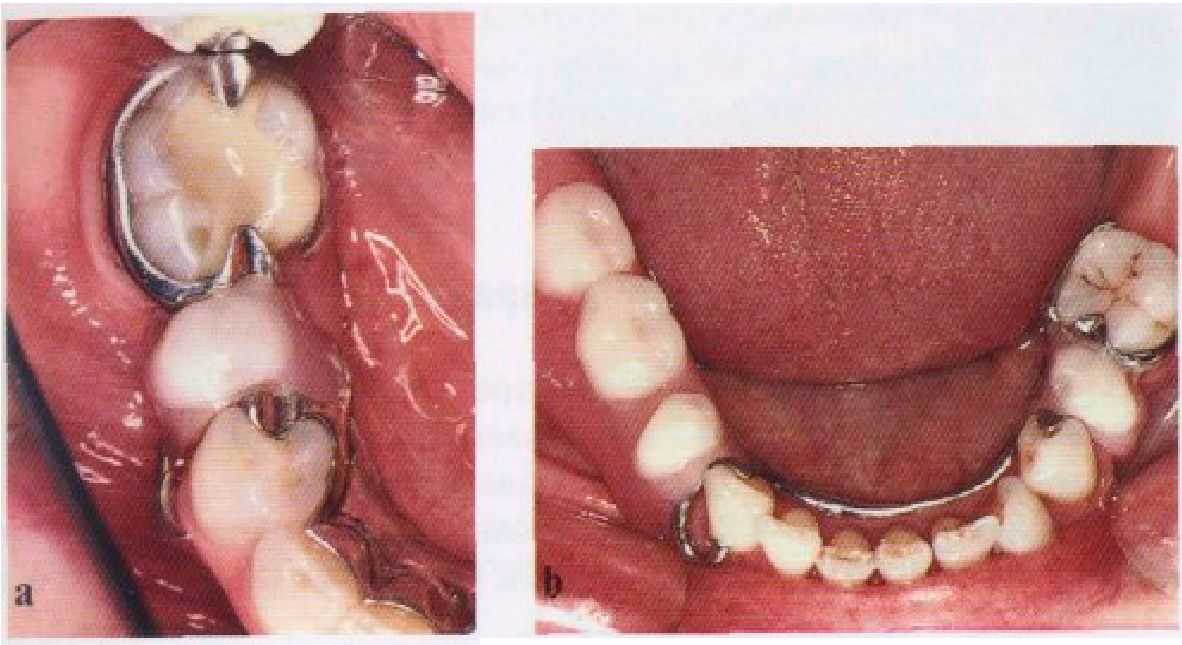

Рис. 3-8. Ретенция частичного съемного протеза, (а) Несмотря на неэффективность кпаммера в области левого первого нижнего премоляра, пациента устраивает ретенция частичного съемного протеза, (б) Два правильно сконструированных кламмера обеспечивают адекватную ретенцию данного частичного съемного протеза.

Включенные дефекты требуют меньшей ретенции, чем концевые. Кроме того, традиционно через несколько лет фиксаторы становятся неэффективными. Тем не менее, пациенты могут не замечать уменьшения ретенции (рис. 3-8). Это подчеркивает важность мышечного удерживания, осуществляемого пациентом, в отдаленные сроки полъзова-

ния протезом. Учитывая их изначальную эффективность, на практике редко возникает необходимость более чем в двух прямых фиксаторах.